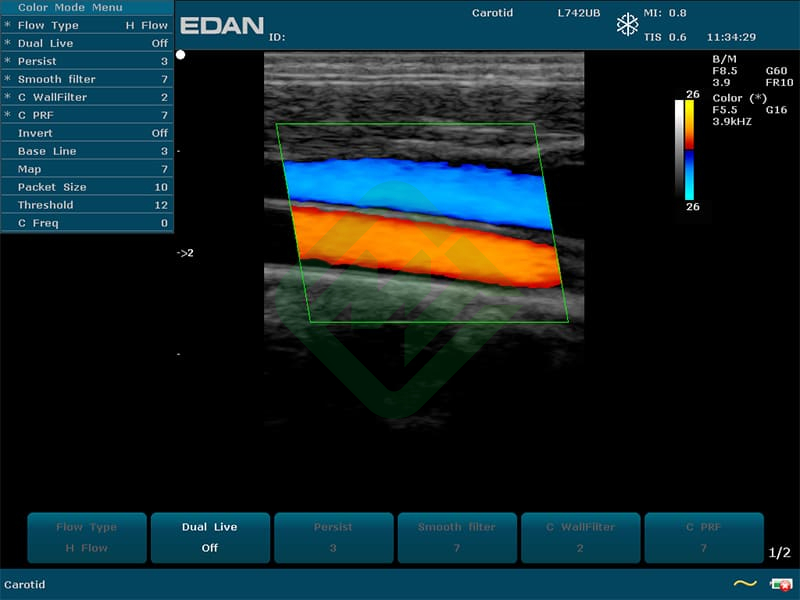

- Режимы сканирования: B, M, CDI, PW, CW, PDI, DPDI или B, M, ЦДК

- Доплерография: импульсно- и постоянно-волновая, направленная энергетическая

— мультичастотные УЗ-датчики: линейный датчик Edan L742UB, конвексный датчик Edan C352UB, фазированный датчик Edan P5-1b

— цветовое доплеровское картирование

— импульсно- и постоянно-волновая доплерография

— направленная энергетическая доплерография

— линейным L742UB: частотный диапазон датчика 5–10 МГц, апертура 40 мм, глубина сканирования 130 мм, количество элементов 128